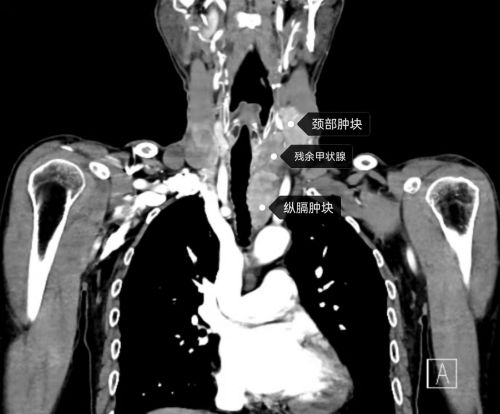

ct显示:双侧甲状腺残余腺体内多发肿块并与气管、食管分界不清,左颈部、纵膈内多发肿块。

入院后的CT和MRI检查显示:双侧甲状腺残余腺体内多发肿块并与气管、食管分界不清,左颈部、纵膈内多发肿块,考虑“多发淋巴结转移”。

乳腺甲状腺外科范培芝主任、张超杰主任医师、何杰副主任医师等讨论认为:患者病情复杂,甲状腺肿块侵犯气管、食管外膜,并包绕颈总动脉;侧颈区淋巴结包绕颈内静脉、迷走神经;纵膈内肿块紧邻主动脉弓、头臂干、左颈总动脉、左锁骨下动脉。加上病情进展十分迅速,如不尽快实施手术,患者将很快面临气管受压导致窒息、食管侵犯无法进食及广泛转移失去手术机会等多种危及生命的风险。